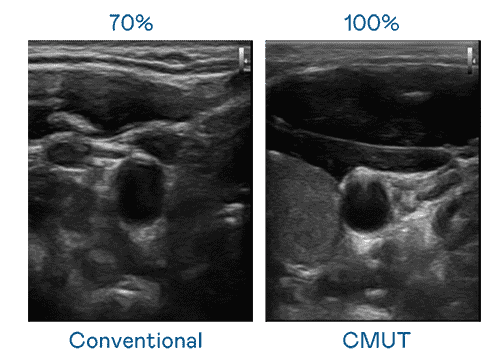

CMUT 技术是一种用电容式微机电元件来产生超音波讯号的技术。。与传统 PZT 压电式技术相比,,CMUT 频宽增加 30%,,,更宽频的超音波讯号让影像解析度大幅提升,,是实现高影像品质医疗超音波扫描、、、、促进精准医疗发展的关键技术。。

大频宽带来超清晰影像

超音波影像的解析度高低,,,首先取决于探头能发出的讯号频宽。。。。赏金国际 CMUT 可提供高清晰的超音波讯号,,提供高频宽、、、、高灵敏度、、、、影像纹理细节更高的超音波影像,,协助医护人员缩短影像判读时间及利用精准的医疗影像进行诊断。。。